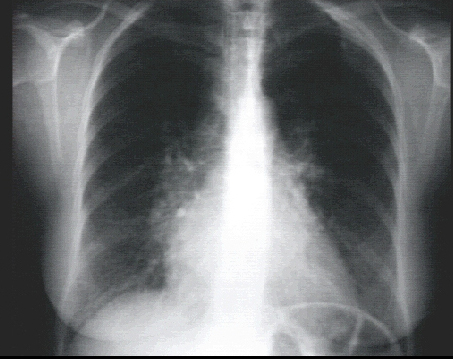

PA view

The PA view demonstrates left atrial enlargement, reflected by the double contour within the heart border, an elevated left mainstem bronchus and an enlarged left atrial appendage, causing straightening of the left heart border. Note also that the cardiothoracic ratio is greater than 50%, reflecting cardiomegaly.